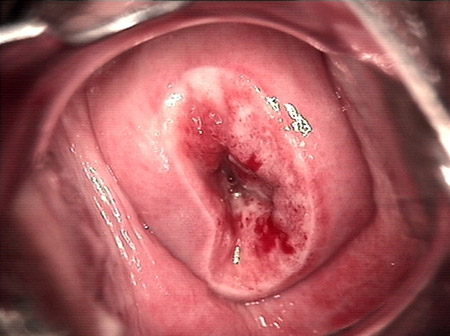

婦科leep錐切手術(shù) CIN2-3

• CIN 2-3 修復后CIN 2-3 修復后